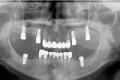

Цифровой рабочий процесс для создания окончательного гибридного протеза с опорой на имплантаты

Гибридные протезы с опорой на имплантаты стали популярным решением при лечении пациентов с не подлежащими восстановлению зубами или полным отсутствием зубов. С момента внедрения остеоинтегрируемых дентальных имплантатов для лечения потери зубов для изготовления несъемных гибридных протезов всего зубного ряда использовались различные ортопедические конструкции и материалы. Хотя такие реставрации могут быть весьма успешными, наиболее частые неудачи связаны с отсутствием места для протеза или с отсутствием пассивного прилегания каркаса, что может привести к сколам, расслоению и/или переломам. В данной статье рассматриваются клинические и лабораторные этапы изготовления окончательных гибридных протезов с опорой на имплантаты с применением шаблонов для снижения объема кости, шаблонов для создания ложа имплантата и немедленной фиксации временного протеза, изготовленного с использованием цифровых технологий.